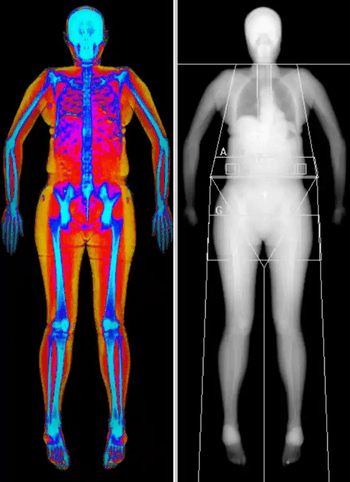

Beställ en remiss för helkroppsscanning i preventivt syfte. Med MR Helkropp får du en helhetsbild av kroppen för att upptäcka eventuella sjukdomar och avvikande fynd i tidigt skede.

Undersökningen är en avancerad och helt strålningsfri magnetkameraundersökning som scannar din kropp hela vägen från hjärnan och ner till bäckenet och tar ungefär 50 minuter att genomföra.

Undersökningen ger dig en möjlighet att få en god överblick av din hälsa. Med hjälp av magnetkamerateknik kan radiologen upptäcka förändringar i kroppens organ och vävnader redan i ett tidigt skede, ofta innan symtom uppstår och innan avvikelser syns i blodprov. Undersökningen är strålningsfri, icke-invasiv och lämpar sig väl för dig som vill ta ett aktivt ansvar för din hälsa, få ökad trygghet eller följa upp tidigare fynd och avvikelser med högsta möjliga precision.

Undersökningen tar ungefär 50–60 minuter och omfattar 9 stycken högupplösta sekvenser som ger en bred men detaljerad översikt av hela kroppen. Här följer de olika områden som analyseras och som radiologen samt läkaren återkopplar på: